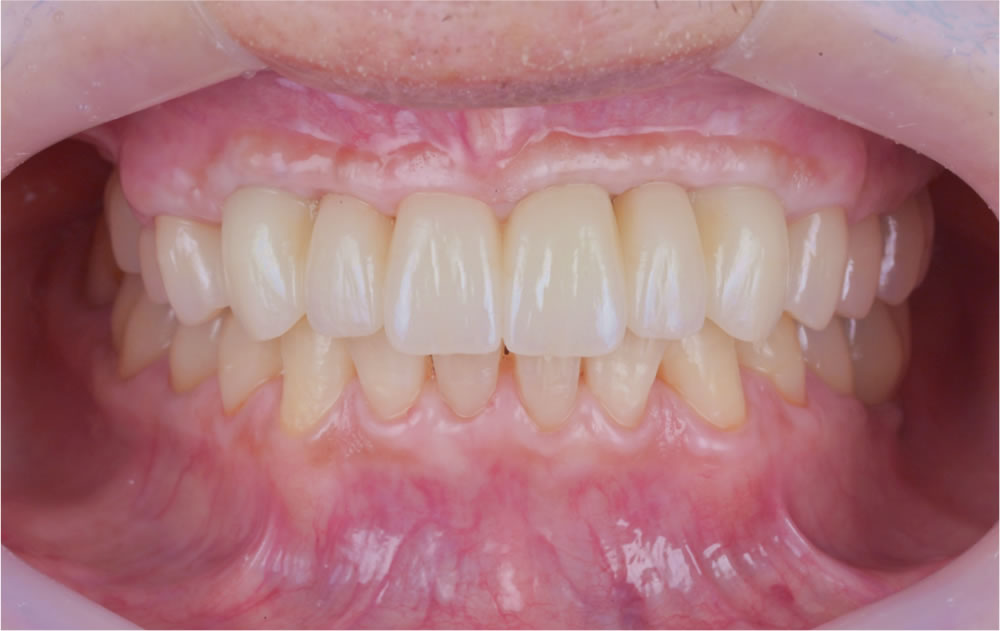

最終的な上部構造(人工歯)を口腔内に装着し、咬み合わせを調整して治療完了となりました。

| 性別・年齢 | 70代男性 |

| 治療期間 | 約1年 |

| 治療回数 | 30回(複数回の外科的な処置が含まれます) |

| 治療費 | 4,400,000円(税込) |